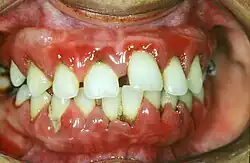

Maladie parodontale

Les maladies parodontales affectent les tissus qui entourent et soutiennent les dents[9]. Elles se manifestent par un saignement ou un gonflement des gencives (gingivite), des douleurs et parfois par une mauvaise haleine. On estime que les parodontites avancés touchent près de 19 % de la population adulte mondiale. Les principaux facteurs de risque sont une mauvaise hygiène bucco-dentaire et le tabagisme.